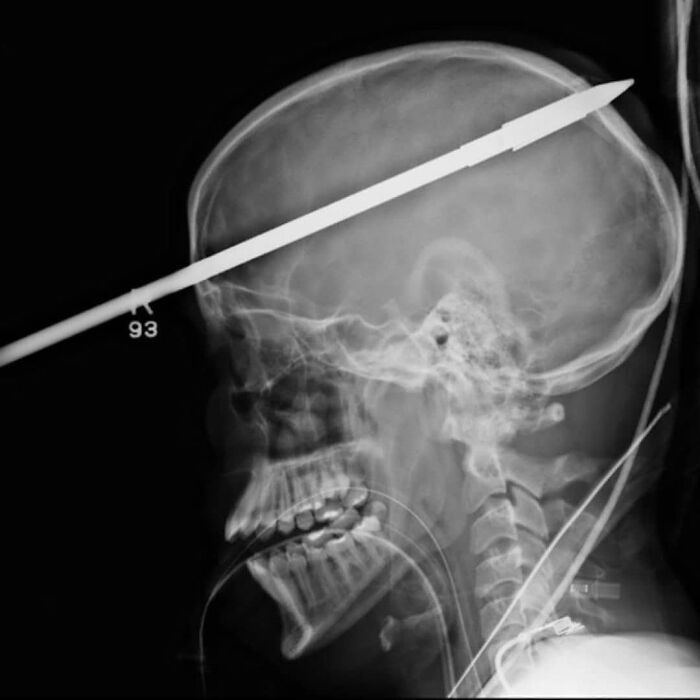

#41 A 16-Year-Old Survied An Accident In Which A Spear Gun His Friend Was Holding Accidentally Discharged

Image credits: medicalpedia